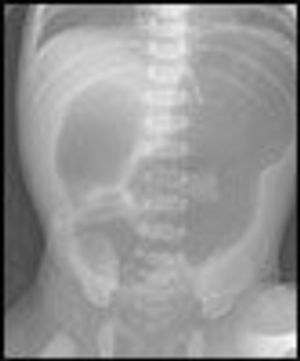

The patient is a female neonate who weighed 2210 g at birth. The mother is an 18-year-old Mexican American (gravida 1, para 0, rapid plasma reagin-nonreactive, rubella-immune, and hepatitis B surface antigen-negative) who has had no regular prenatal care. She was admitted via the emergency department to labor and delivery after spontaneous rupture of fetal membranes at home.